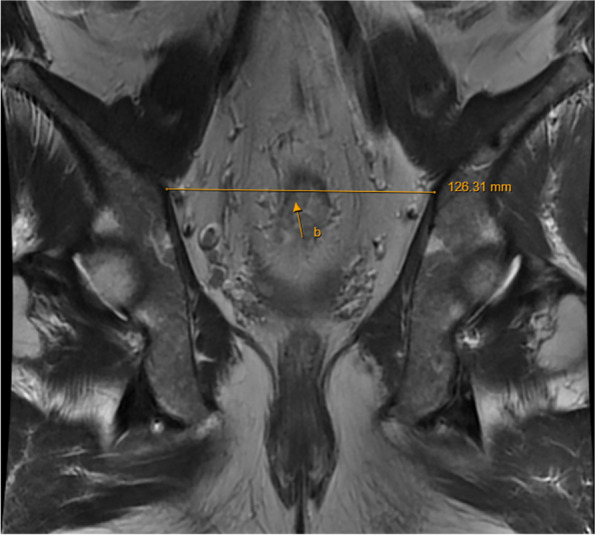

Fig. 2.

Coronal MRI of the pelvis: b pelvic entrance transverse diameter

| (b) Pelvic entrance transverse diameter | The maximum distance between the iliopubic lines on both sides (Fig. 2) | [6, 20] |